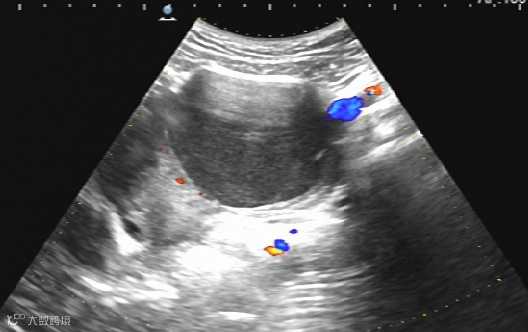

卵巢巧克力囊肿硬化治疗:

治疗前

治疗后